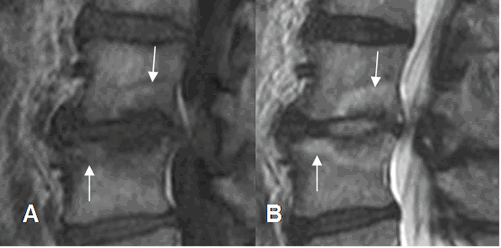

Fig 116. Cambios degenerativos Modic tipo I.

A: RM sagital en T1 y B: RM sagital en T2. Cambios degenerativos en las placas terminales, hipointensos en T1 e hiperintensos en T2.